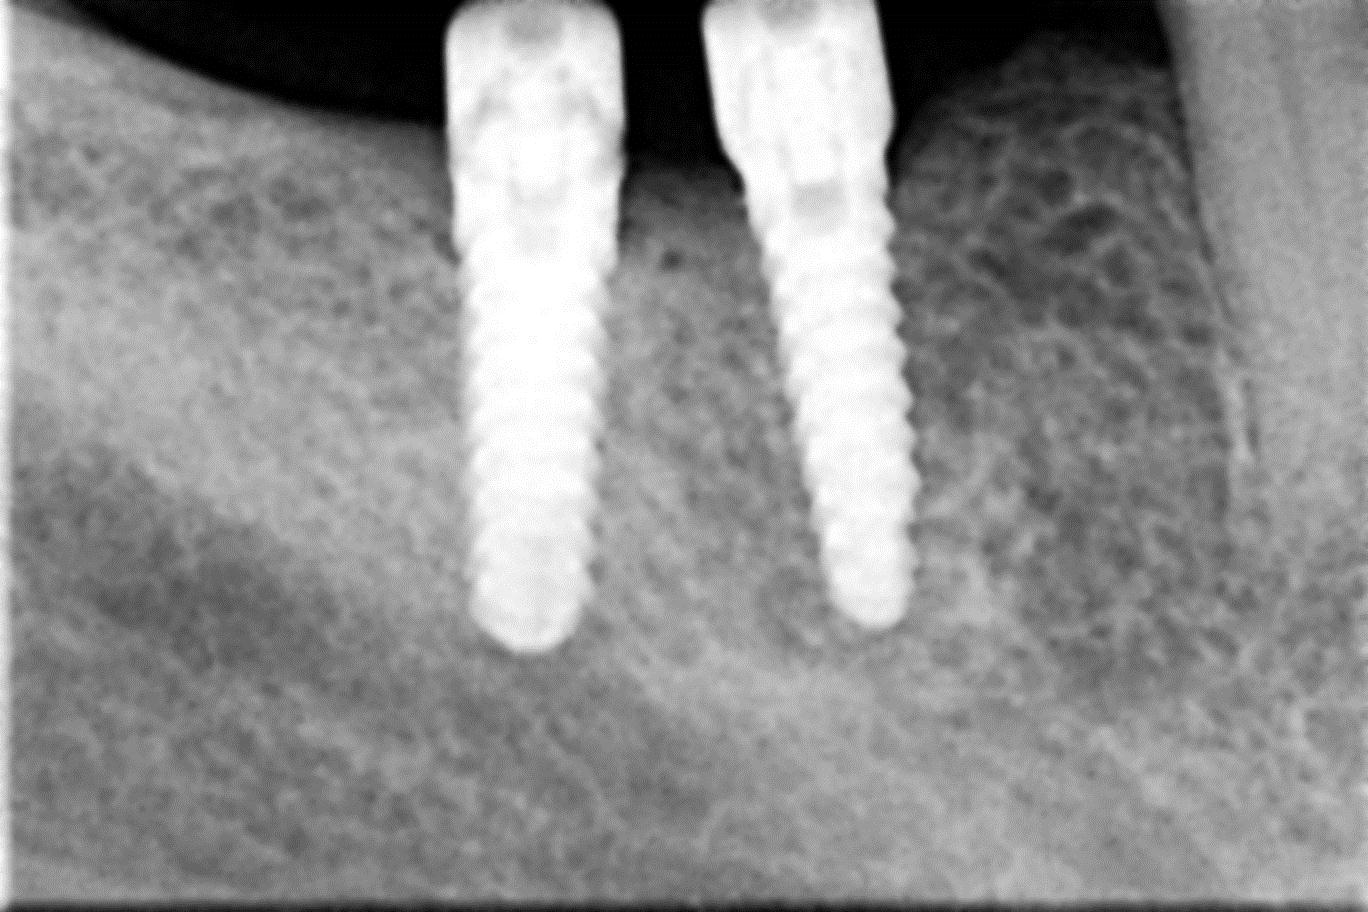

• Zavedení implantátu do kosti čelisti

• Zahojení do kosti – 3-4měsíce(v některých případech i déle – doplňování kosti)

Zavedení implantátů do kosti je většinou ambulantní chirurgický výkon, srovnatelný s vytržením zubu a většinou se provádí v lokální anestézii. Ve výjimečných případech je možné použít i analgosedaci či celkovou narkózu. Operaci provádí zubní lékař-implantolog při dodržení všech podmínek sterility pro operaci. Nástroje pro tuto operaci jsou konstruovány tak, aby výkon byl šetrný vůči kosti a zavedení implantátu bylo provedeno ve velmi krátké době. Díky kvalitní anestézii je výkon nebolestivý. Aby byl pooperační otok co nejmenší, je potřeba operovanou oblast chladit, dle poučení ošetřujícího lékaře. Lékař také ordinuje podle potřeby léky na bolest, případně antibiotika.

Průměrná doba hojení implantátů před provedením definitivního protetického ošetření je 3-4 měsíce, v případech, kde je nutné doplnit chybějící kost (různé metody, postupy a materiály) – tzv. augmentace) se může doba hojení prodloužit na 8-12 měsíců. S tím je pacient vždy předem seznámen svým lékařem.